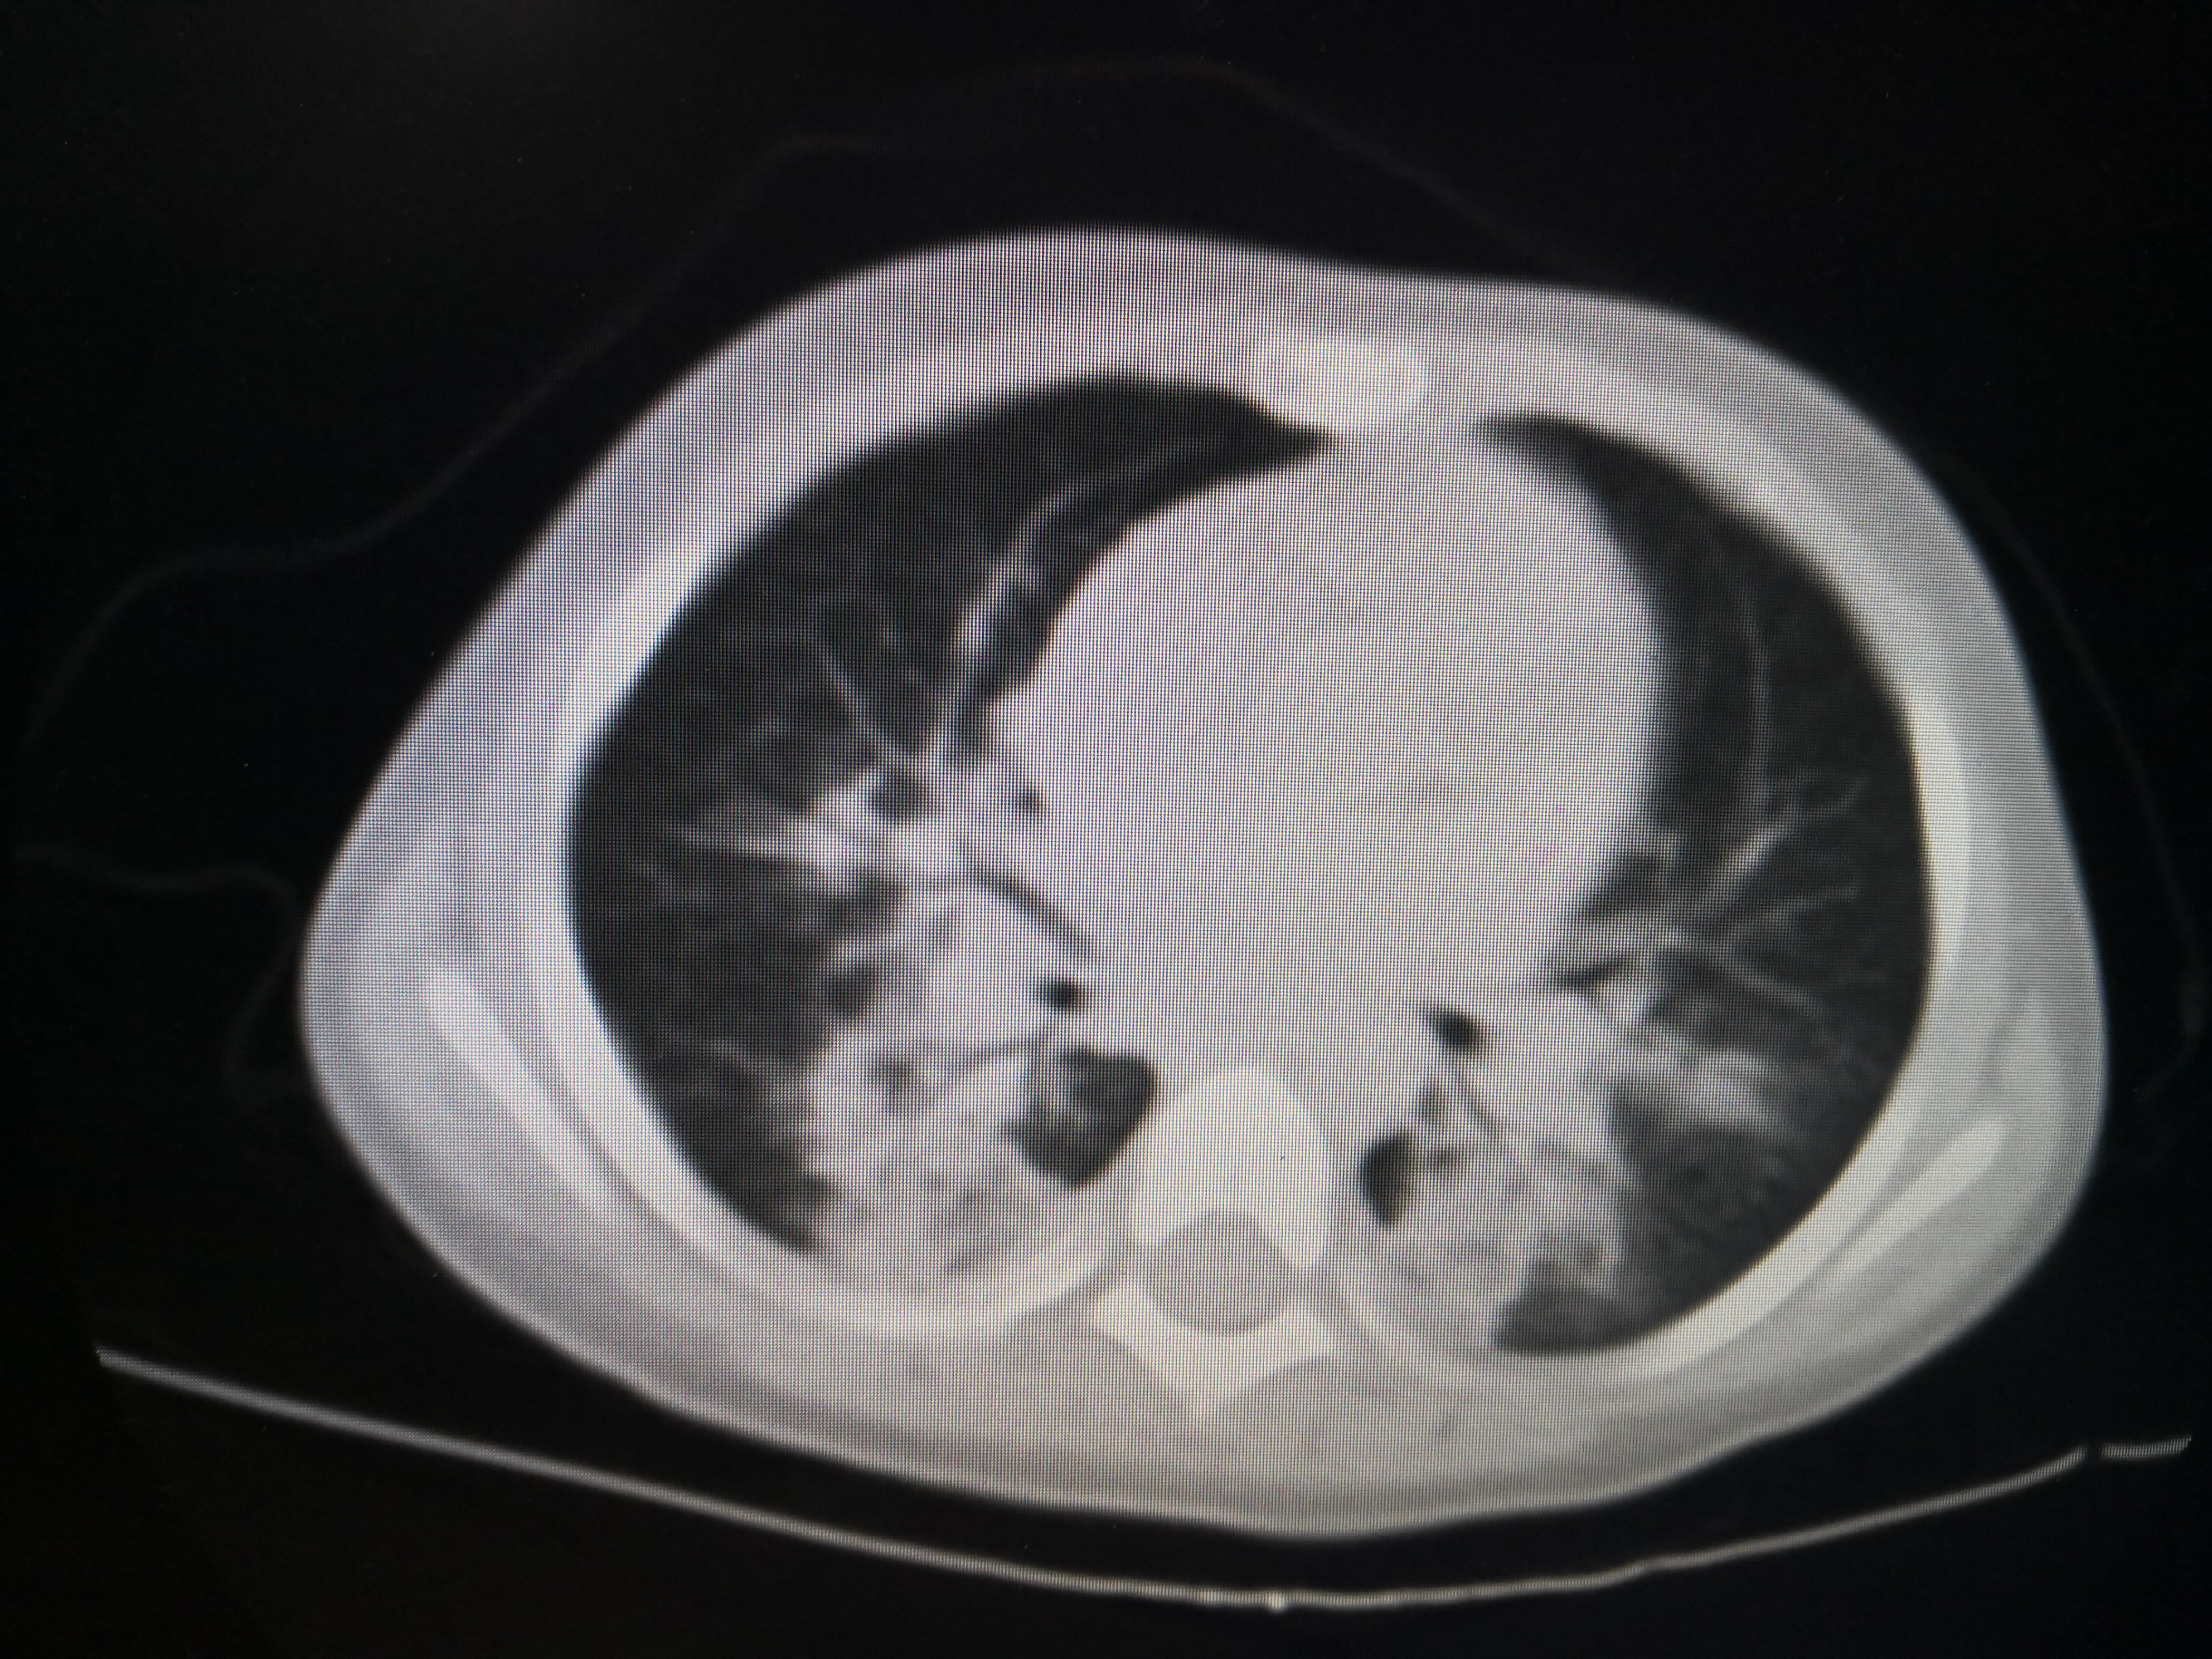

双肺炎症非常明显。CT结果出来后立即予以支气管镜灌洗治疗,在灌洗治疗过程中发现小朋友气管支气管里面大量黑色粪渣伴有较多黄色粪汁,遂将每个肺叶肺段灌洗干净,一周内完成2次支气管镜的灌洗治疗。第二次灌洗的时候双肺已经比较干净。出院后又口服了两周的强力抗生素。两周后复查胸部CT,结果如下

经过积极的救治,该小朋友双肺基本完全恢复正常。值得庆幸的是未留下任何肺部及大脑等重要脏器的后遗症。在这个小朋友的治疗过程中非常重要的治疗措施就是积极的予以支气管镜的灌洗治疗,及时清除了肺及气管支气管内的粪渣及粪汁,才能使得小朋友顺利康复!